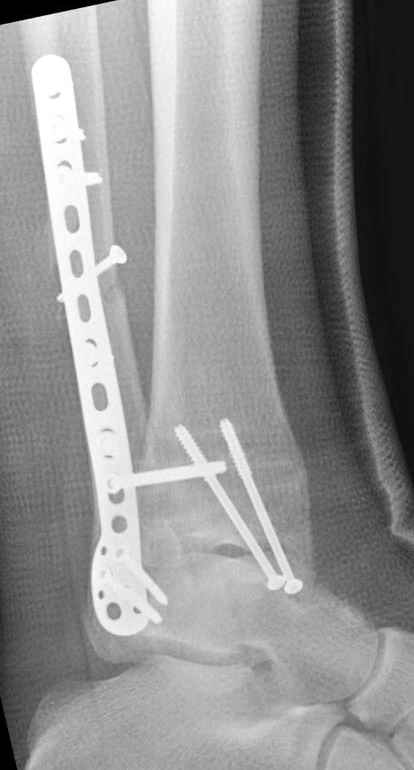

Если до сих ничего не сделано, с артродезом сустава в данный момент я бы повременил, на выставленных январских снимках хорошо сохранившийся сустав, а в "мортиз" (трехчетвертной) и на боковых снимках не менее 5 мм укорочение малоберцовой кости. Косые переломы лучше фиксировать пластинами, как то мы разбирали случай, где было отмечено, что это закон "таранная кость всегда следует за малоберцовой".

В данном случаи я бы уговорил больного на реконструкцию, для этого после удаления шурупов, спереди очистить от рубцов синдесмоз, несросшуюся наружную лодыжку - остеотомия по линии перелома и компрессирующий (lagging technique) кортикальный шуруп 3.5 мм по поперечнику остеотомии. Следующий этап - восстановление длины малоберцовой за счет удлинения, сделать поперечную остеотомию где-то на уровне сантиметр выше вашего синдесмозного шурупа, наложить длинную пластинку, прикрепить пластину за дистальный конец двумя или тремя шурупами; сохраняя контакт пластины с костью, имеющимся

compression&tension device AO system (при отсутствии любой lamina spreader подойдет, создать дистанцию между пластиной и шурупом, проведенным проксимальнее пластины) толкая проксимальный отдел пластины, низвести пластину, мортиз рентгенограмма подскажет на сколько. Если заранее сделать предоперационный план (ренгенограмма другой стороны), тогда точно можно определить, на сколько вам необходимо сделать поперечную остеотомию малоберцовой кости, для закрытия создавшегося дефекта.

Убедившись, что желаемая длина восстановлена, окончательная фиксация пластины, при этом через пластину пару 3.5 мм шурупов на синдесмоз, предпочтительно в четыре кортекса и оставить на 3 мм длиннее, если под нагрузкой синдесмотический шуруп сломается, сломанный конец легче удалить с медиальной стороны.

Медиальная сторона не в нагрузочной зоне, и там большая дыра - если есть 2.7 мм шурупы, или пару спиц в ваших условиях или методика Лазарева. Необходимо уделить внимание к мягким тканям, обнажается кость с латеральной стороны и у места где проводится остеотомия.

После 5-6 недели после травмы сделана повторная операция, обошлись без удлинения малоберцовой.